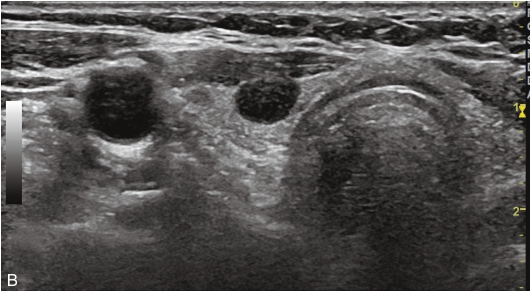

女性,73岁,发现颈部肿胀1个月,伴多汗、心悸、睡眠不佳。甲状腺功能检查:FT3 8.21nmol/L,FT4 20.14nmol/L,TSH 0.001 1μIU/ml。 131 I核素扫描结果提示高功能腺瘤。

甲状腺大小形态失常,左叶增大。甲状腺左叶内见一个等回声结节,边界清楚,形态规则,内部呈均匀等回声,纵横比<1,结节内未见钙化,后方回声无明显变化。CDFI显示结节内有丰富的血流信号,以周边供血为主,见图1-3-26。

图1-3-26 甲状腺高功能腺瘤常规超声表现

A.甲状腺左叶等回声结节纵切面灰阶超声图像;B.甲状腺左叶等回声结节CDFI图像

图像描述:甲状腺左叶结节增强早期呈周边环状增强,向中央逐渐扩张,增强晚期呈均匀稍高增强,见图1-3-27。

图1-3-27 甲状腺高功能腺瘤超声造影图像